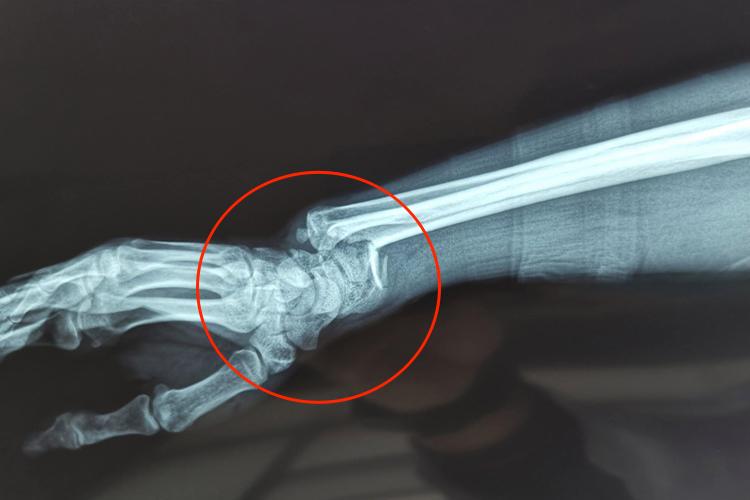

柯力氏骨折一般是指桡骨下端骨折,伤后会有剧痛、肿胀,活动受限。检查局部有明显压痛,并出现典型畸形姿势,侧面观呈“银叉”畸形,正面观呈“枪刺刀”畸形。X线可见骨折远端向桡侧、背侧移位,近端向掌侧移位,常伴有桡尺远侧关节脱位或尺骨茎突撕脱。

柯力氏骨折发生在桡骨下端3cm范围内,多是跌倒时,前臂旋前,腕关节背伸,手掌保护性着地所致。